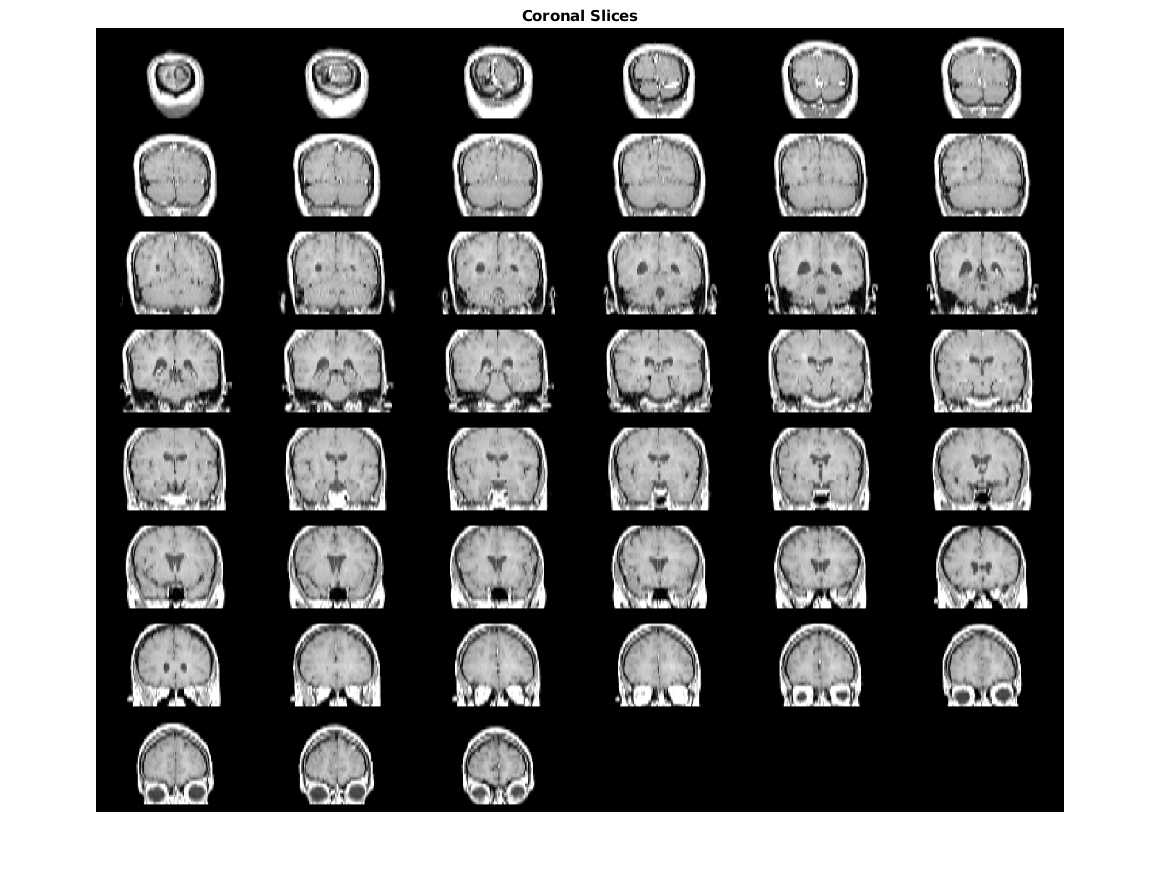

Slices contains

Slices contains 142 фотографий